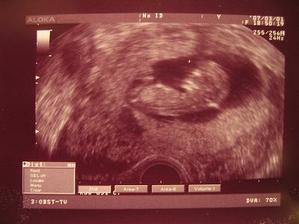

Náš Vohnoutek 🙂

Kontrola 18.1...zatím v pořádku. Ještě, ale nemáme srdeční akci.